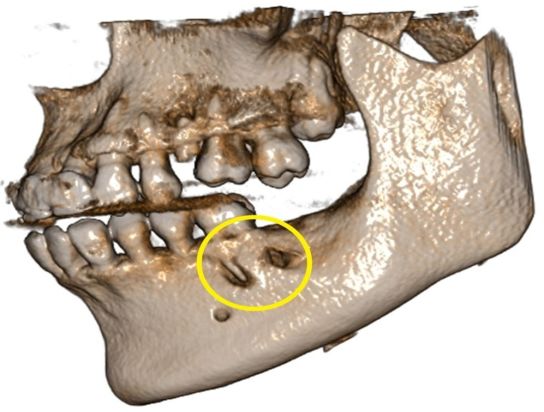

在CBCT扫描所得的影像中,可以清晰地看到,小野最后一颗大牙的根尖有明确的暗影,所指示的结果为该牙根尖区域已经被炎症所波及,根尖的骨质已经被吸收。

在3D的图像中更是触目惊心,原本完整的下颌骨表面出现了两个深坑,根尖骨质已经被“腐蚀”掉了!

至此真相终于大白,结合所有的检查,患者脸颊部位硕大的“痘痘”和口腔内脓包的来源,都一一指向这颗大牙,引起小野如此破相的原因就是这颗大牙闯的“祸”!

其实这颗可怕的“痘痘”,并不是真正的青春痘,它的真身其实是这颗烂牙因根尖周炎久病不治,拖延病情而导致的瘘管!